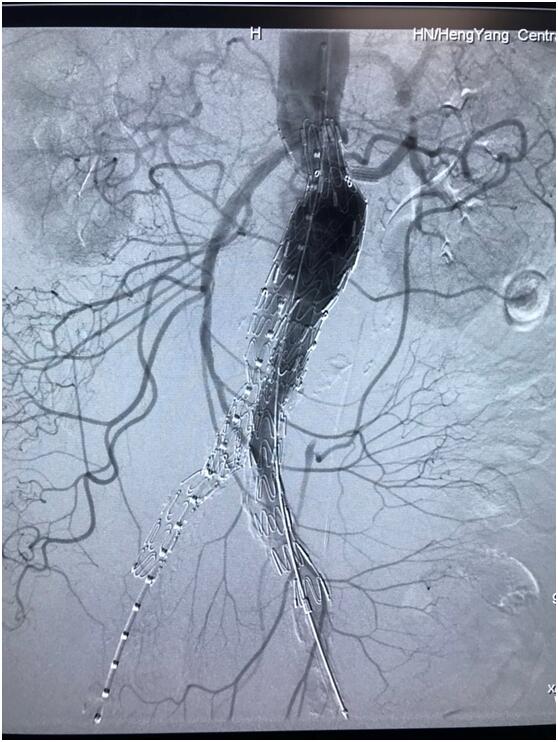

患者因腹部搏動(dòng)性腫塊行成已有4年,伴右下腹疼痛6小時(shí)入院,既往有高血壓病史,患者入院后血壓177/96mmHg,醫(yī)護(hù)人員隨即予以控制血壓、止痛處理,CTA檢查提示患者有腎下腹主動(dòng)脈瘤,合并心 、肝 、肺 、腎等重要臟器疾患,根據(jù) Laplace定律,動(dòng)脈瘤直徑越大壓力越大,老人動(dòng)脈脆弱,動(dòng)脈瘤隨時(shí)有破裂的可能性,其危險(xiǎn)性大。血管介入科排除各種困難,在麻醉科協(xié)作下行腹主動(dòng)脈瘤覆膜支架隔絕術(shù)(“褲衩”支架植入),手術(shù)持續(xù)了1個(gè)半小時(shí),患者術(shù)后安返病房,麻醉醒后露出了微笑,向醫(yī)務(wù)人員伸出大拇指。

血管介入科行腹主動(dòng)脈瘤覆膜支架隔絕術(shù)(“褲衩”支架植入)。圖3